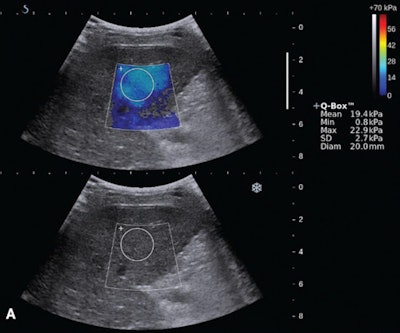

Shear-wave elastography (top) and endoscopy (bottom) of a 59-year old woman with a F2 varix. The median liver stiffness on shear-wave elastography was 19.3 kPa. Images courtesy of the Journal of Ultrasound in Medicine.In other study results, liver stiffness also yielded the highest area under the curve for predicting esophageal varices in patients without splenomegaly. The difference with platelet count/spleen diameter was statistically significant (p = 0.034) Liver stiffness also had the highest area under the curve for predicting esophageal varices in patients with splenomegaly, but that difference did not reach statistical significance (p = 0.292).